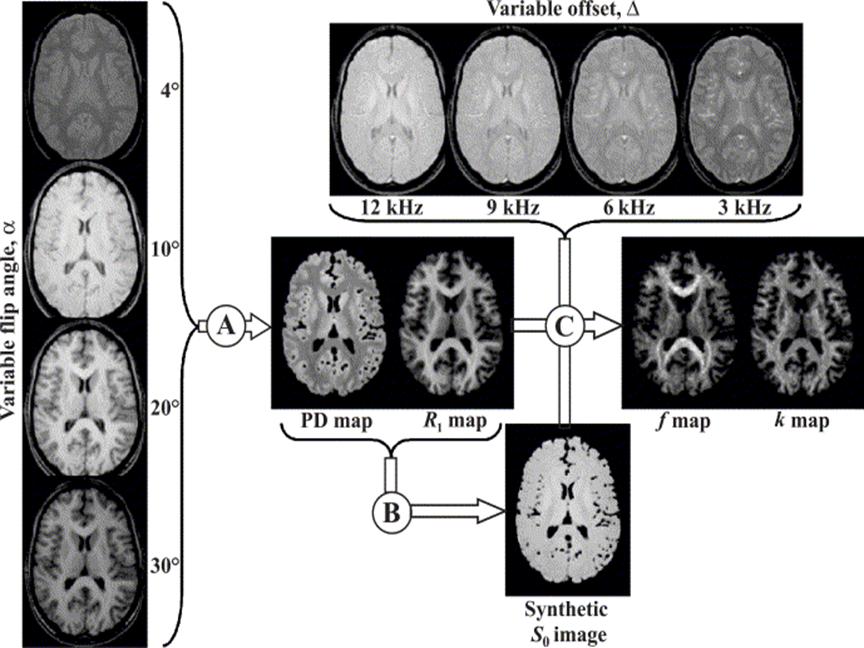

Figure

1. Diagram of k and f map

generation.

Figure 1 displays a summary of the outflow of the process. In the

first part, we acquire data with four different flip angles and using these

data we create PD and R1 maps (this step is labeled as A

in Figure 1). In the second part, instead of changing the flip angle to get

contrast in the measured data, we use a magnetization transfer pulse. By

varying the offset frequency at which the pulse is applied, we get four

different-contrast images. Using these data and the previous estimation

results, we are able to generate k and f maps (this step is labeled as C in

Figure 1). The creation of the synthetic image shown with letter B in Figure 1

is required for normalization purposes, to increase statistical stability of

the estimation process. The details of the estimation steps are explained in

later sections.